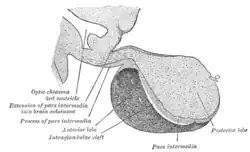

Median sagittal through the hypophysis of an adult monkey. Semidiagrammatic. | |

Structure

The pituitary gland sits in a protective bony enclosure called the sella turcica (Turkish chair/saddle). It is composed of three lobes: the anterior, intermediate, and posterior lobes. In many animals, these lobes are distinct. However, in humans, the intermediate lobe is but a few cell layers thick and indistinct; as a result, it is often considered part of the anterior pituitary. In all animals, the fleshy, glandular anterior pituitary is distinct from the neural composition of the posterior pituitary.

The anterior pituitary is composed of three regions:

- Pars intermedia

- The pars intermedia (intermediate part) sits between the pars distalis and the posterior pituitary, forming the boundary between the anterior and posterior pituitaries. It is very small and indistinct in humans.